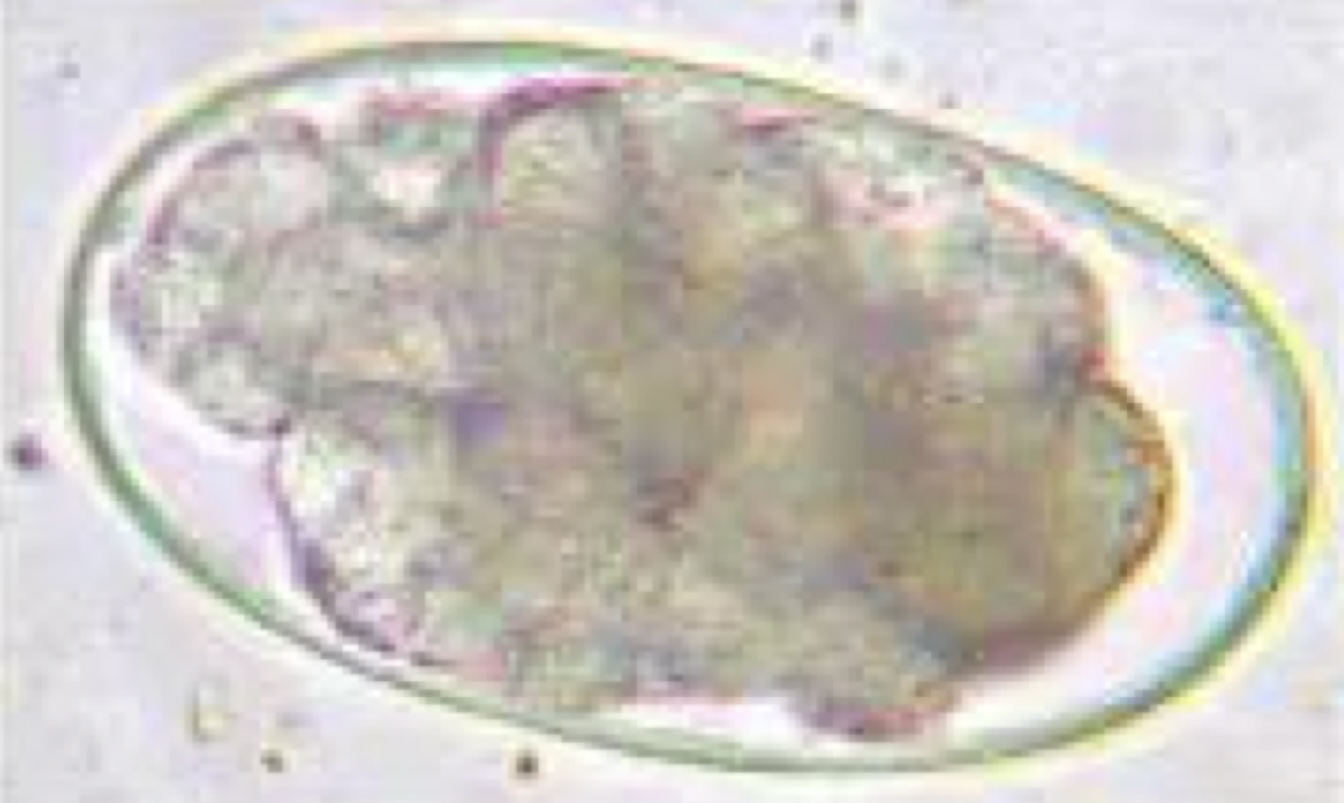

Trichuris vulpis - canine whipworm

Capillaria plica (K9) and Capillaria feliscati (feline) - bladder worm

Trichuris spiralis - swine

Oxyuris equi - equine pinworm

Dioctophyma renale - canine kidney worm